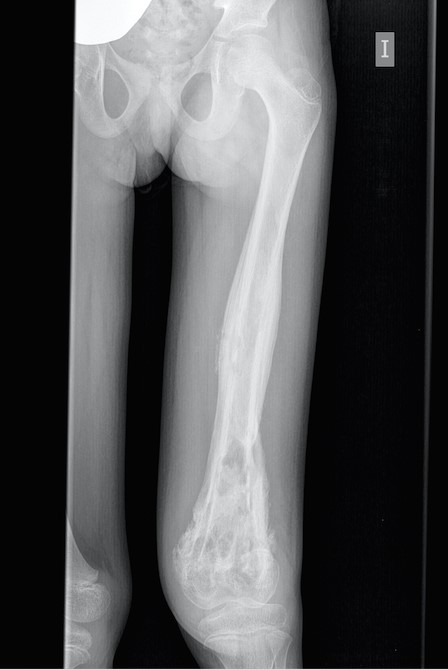

Se realiza una primera valoración de la paciente en nuestra consulta de Pediatría de Atención Primaria. El padre de la niña refiere que hace tres meses presentó una caída desde la cama, no presenciada por ellos, y desde entonces rechaza la deambulación. Además, presenta pérdida importante de peso no cuantificada. En la exploración destaca la tumefacción en muslo izquierdo, dolorosa a la palpación, y aumento de la temperatura local. No presenta adenopatías palpables ni masas a nivel abdominal. Se remite a urgencias para estudio. En la radiografía de extremidad inferior izquierda, en fémur distal, se observan áreas líticas mal definidas, junto con reacción perióstica (Fig. 1). Se plantea diagnóstico diferencial de fractura o tumor. Durante el ingreso se completa el estudio con gammagrafía ósea, en la que se aprecia aumento de la captación en tercio medio y distal de fémur izquierdo. Tras la realización de la resonancia magnética del fémur izquierdo, las imágenes sugieren osteomielitis crónica como opción más probable y, en segundo lugar, sarcoma de Ewing. Para poder diferenciarlo se realiza biopsia de la lesión, obteniéndose en su cultivo crecimiento de S. aureus. Tras realizarse su estudio anatomopatológico, es informado como osteomielitis crónica sin signos de malignidad. Se administra tratamiento antibiótico intravenoso con cloxacilina durante 43 días, junto con limpieza de la lesión en el quirófano, y aplicación de esponjas de gentamicina intralesionales. Se realiza valoración por Gastroenterología Pediátrica, iniciándose suplementación con batidos hipercalóricos e hiperproteicos. Evoluciona favorablemente, con disminución de la lesión y del dolor, junto con mejoría de la movilidad de la extremidad. Es dada de alta con tratamiento antibiótico oral, y seguimiento en consultas de Enfermedades Infecciosas, Traumatología y Gastroenterología Pediátricas.

| Figura 1. Radiografía de extremidad inferior izquierda. En tercio medio y distal de fémur se observan áreas líticas y reacción perióstica adyacente, junto con signos indirectos de derrame articular |